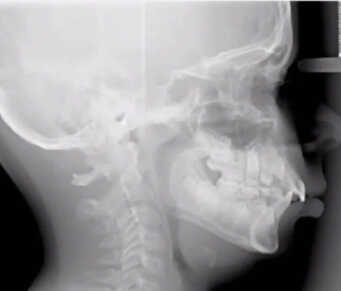

While obstructive sleep apnea is commonly associated with adults, it is important to recognize that children can also be affected by this condition. Pediatric obstructive sleep apnea refers to a sleep disorder in which a child’s breathing is partially or completely obstructed during sleep, leading to disrupted breathing patterns and inadequate rest. The underlying cause of this condition is often the narrowing or blockage of the upper airway during sleep.

Enlarged tonsils or adenoids are frequent culprits of obstructive sleep apnea in children. However, other factors, such as genetic predisposition, nasal allergies, Down syndrome or cerebral palsy, may also increase the risk of pediatric sleep apnea.